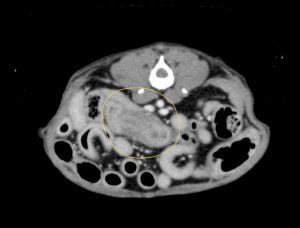

腹部超音波検査で、回盲部(小腸と大腸の境目)の腸壁の肥厚を認め、細胞診で腫瘍性疾患を疑う結果でしたので、CT検査で転移の有無を確認し、回盲部切除を行いました。

病変のCT画像

病変のCT画像